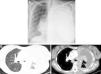

Caso clínicoUma gestante de 36 anos de idade, fumadora ligeira, foi admitida no hospital às 27 semanas de gestação, em agosto de 2010, com uma história de mal-estar geral, fadiga, dispneia de esforço, tosse seca e toracalgia pleurítica esquerda desde o segundo trimestre de gestação. Sem medicação regular reportada. Ao exame objetivo, a doente apresentava baixo performance status (PS 3). A auscultação pulmonar revelou redução dos sons respiratórios no campo pulmonar esquerdo. A telerradiografia torácica evidenciou opacidade pulmonar total esquerda com desvio contralateral do mediastino, sugestivo de derrame pleural (fig. 1A). A toracocentese e biopsia pleural realizadas revelaram o diagnóstico de adenocarcinoma do pulmão metastático. O estudo imunohistoquímico mostrou positividade para CK7, CK8/18 e napsina, e negatividade para CK20, recetores de estrogénios e progesteronas. O teste para a mutação EGFR (sequenciação direta de ADN) foi negativo.

A. Telerradiografia torácica mostrou opacidade total do pulmão esquerdo com desvio contralateral do mediastino. B. TC torácica revelou uma enorme massa no hilo pulmonar esquerdo, envolvendo a artéria pulmonar e o brônquio principal esquerdo, bem como um derrame pleural esquerdo de grande volume com espessamento pleural.

Após o parto, a doente realizou TC toraco-abdominal, a qual revelou uma massa hilar esquerda de grandes dimensões sem plano de clivagem com estruturas vasculares, múltiplos implantes na pleura mediastínica e derrame pleural esquerdo de grande volume (fig. 1B), para além de múltiplas metástases ósseas e hepáticas. Em setembro de 2010, foi iniciada quimioterapia de primeira linha com carboplatino e vinorrelbina oral (AUC 5 e 60mg/m2, respetivamente). O ácido zolendrónico endovenoso também foi prescrito. Após 4 sessões de quimioterapia, e apesar de alguma melhoria clínica, foi documentada progressão com disseminação do atingimento ósseo e manifestações neurológicas de paraplegia e distúrbios dos esfíncteres (fig. 2.). Subsequentemente, a doente foi submetida a quimioterapia de segunda linha com pemetrexedo (500mg/m2), e radioterapia torácica (T4-T10) (30Gy/12 sessões), mas sem eficácia clínica.